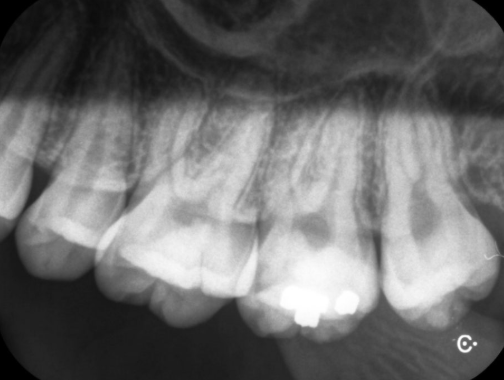

개별 치아를 촬영하는 "디지털 표준촬영" 방사선 사진이며 3 μSv 입니다.

치과에 처음 내원하시면 찍는 일명 큰사진으로 불리는 "파노라마 촬영"이며 10 μSv 입니다.

표준촬영 3장과 파노라마 촬영 1장은 거의 맞먹는 방사선량을 보입니다.